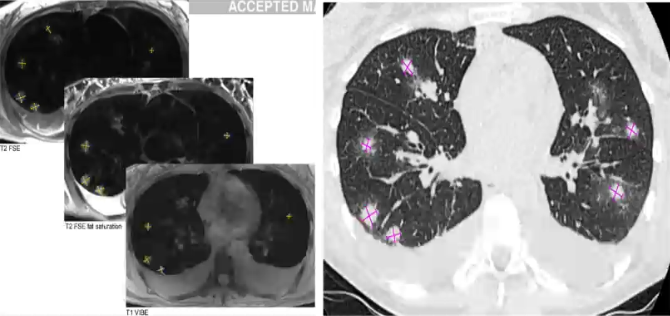

❖ MRI检出肺结节,特别是较大结节(>5mm),与CT接近

❖ 但MRI不能检出磨玻璃影

❖ MRI无辐射,更适合用于真菌结节治疗后随访